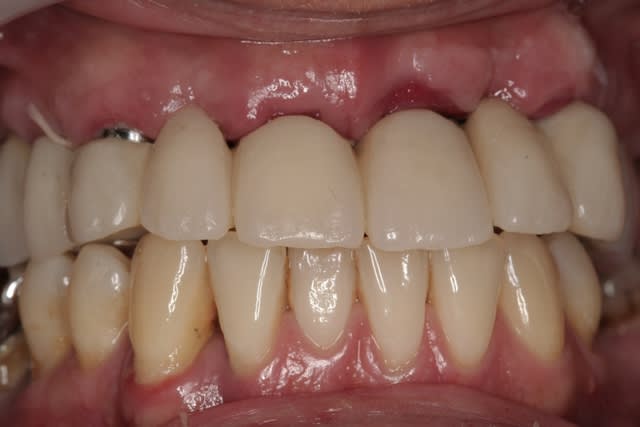

revenons en plutôt au sujet: une MCI, une patiente, et voilà la cicat à 3jours car je viens de la revoir avant ma semaine de congés (pas de pb, s'il y a quoi que ce soit elle a mon n° de portable...)

j'ai remis la photo juste post chir que vous jugiez vous même du repositionnement de la gencive qui est en train de se faire...;-)

je pense que çà va être bien joli pour le définitif...;-)